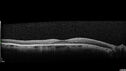

Macular schisis with no leakage on FA - Presumed Nerve pit maculopathy111 views73-year old female. Had treatment trial with Eylea with no benefit (4 months). Vision is 20/32 in left eye and has remained there (with a dense cataract).

Macular schisis with no leakage on FA - Presumed Nerve pit maculopathy110 views73-year old female. Had treatment trial with Eylea with no benefit (4 months). Vision is 20/32 in left eye and has remained there (with a dense cataract).

Macular schisis with no leakage on FA - Presumed Nerve pit maculopathy109 views73-year old female. Had treatment trial with Eylea with no benefit (4 months). Vision is 20/32 in left eye and has remained there (with a dense cataract).

Macular schisis with no leakage on FA - Presumed Nerve pit maculopathy108 views73-year old female. Had treatment trial with Eylea with no benefit (4 months). Vision is 20/32 in left eye and has remained there (with a dense cataract).